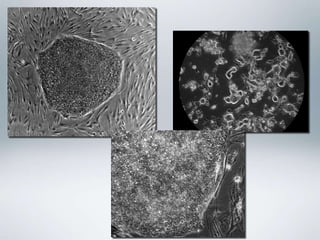

Zer dira? • Zelula-amakorganismo zelulanitz guztietan agertzen diren zelulak dira, guztiz ezberdindu edo espezializatuak. Mitosian bidez zatitzeko gaitasuna dute eta zelula espezifiko edo zelula ama berriak birsortzen dituzte. • Beste zelula mota batzuk sortzeko gaitasuna dute, zelula mota horiekin giza gorputzeko ehunak eratuz.

Sailkapena• Ama-zelula helduak: •Ehun helduetan dauden zelula somatikoak dira. • Multipotenteak dira, hartzen dituzten ehunetako zeluletan ezberdindu daitezkeelako. • Ehun helduetako zelulak berriztatzea da haien lana, organoak etengabe birsortzeko eta lesioak konpontzeko. • Hezur muineko eta zilbor-hesteko zelula ama helduak jada erabiltzen dira terapietan; leuzemia artatzeko, adibidez.

• Ama-zelula enbrionarioak: •Embrioiaren blastozisto (desberdintze prozesurik hasi ez duten enbrioi goiztiarra) fasearen barneko masa zelularra da. • Pluripotenteak. • Minbizia, diabetesa, bizkarrezur muineko lesioak, esklerosi anizkoitza eta beste hainbat gaitz sendatu eta artatzeko erabilgarriak. • Enbrioietatik hartzen dira; zehatzago blastozitoetatik.